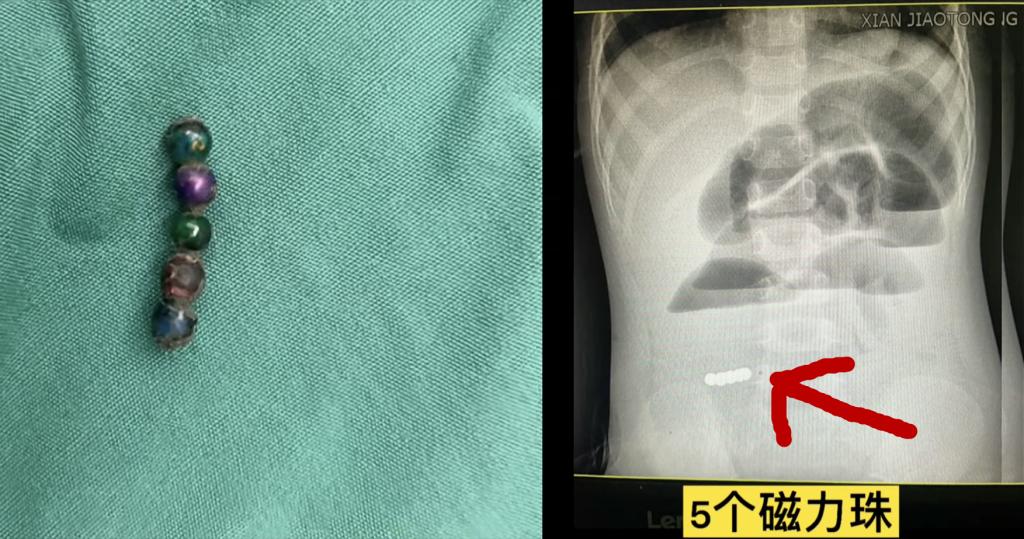

近年来,交大二院小儿外科时常遇到各类消化道异物患儿前来就诊,有的误吞硬币卡在胃里,有的误食磁力珠最后导致消化道穿孔,有的误食玻璃弹珠,有的误食纽扣电池,误食各种“核”后卡在消化道的患儿更是层穷不出。在此,医生也提醒广大宝爸宝妈,一定要看好小朋友,尤其是“什么都往嘴里放”的低龄幼儿。稍不留神,就可能造成不可逆的后果。

3、高危物品妥善保管:硬币、纽扣电池、缝线针、棉棒或牙签等;尽量选择体积较大、无锐角、无磁性的玩具,拒绝危险性玩具,如磁力珠、水养球等。婴幼儿玩玩具时,成人全程监护,勿走神;幼儿衣物宜简单舒适,不让奇异的饰品引其好奇、撕扯。